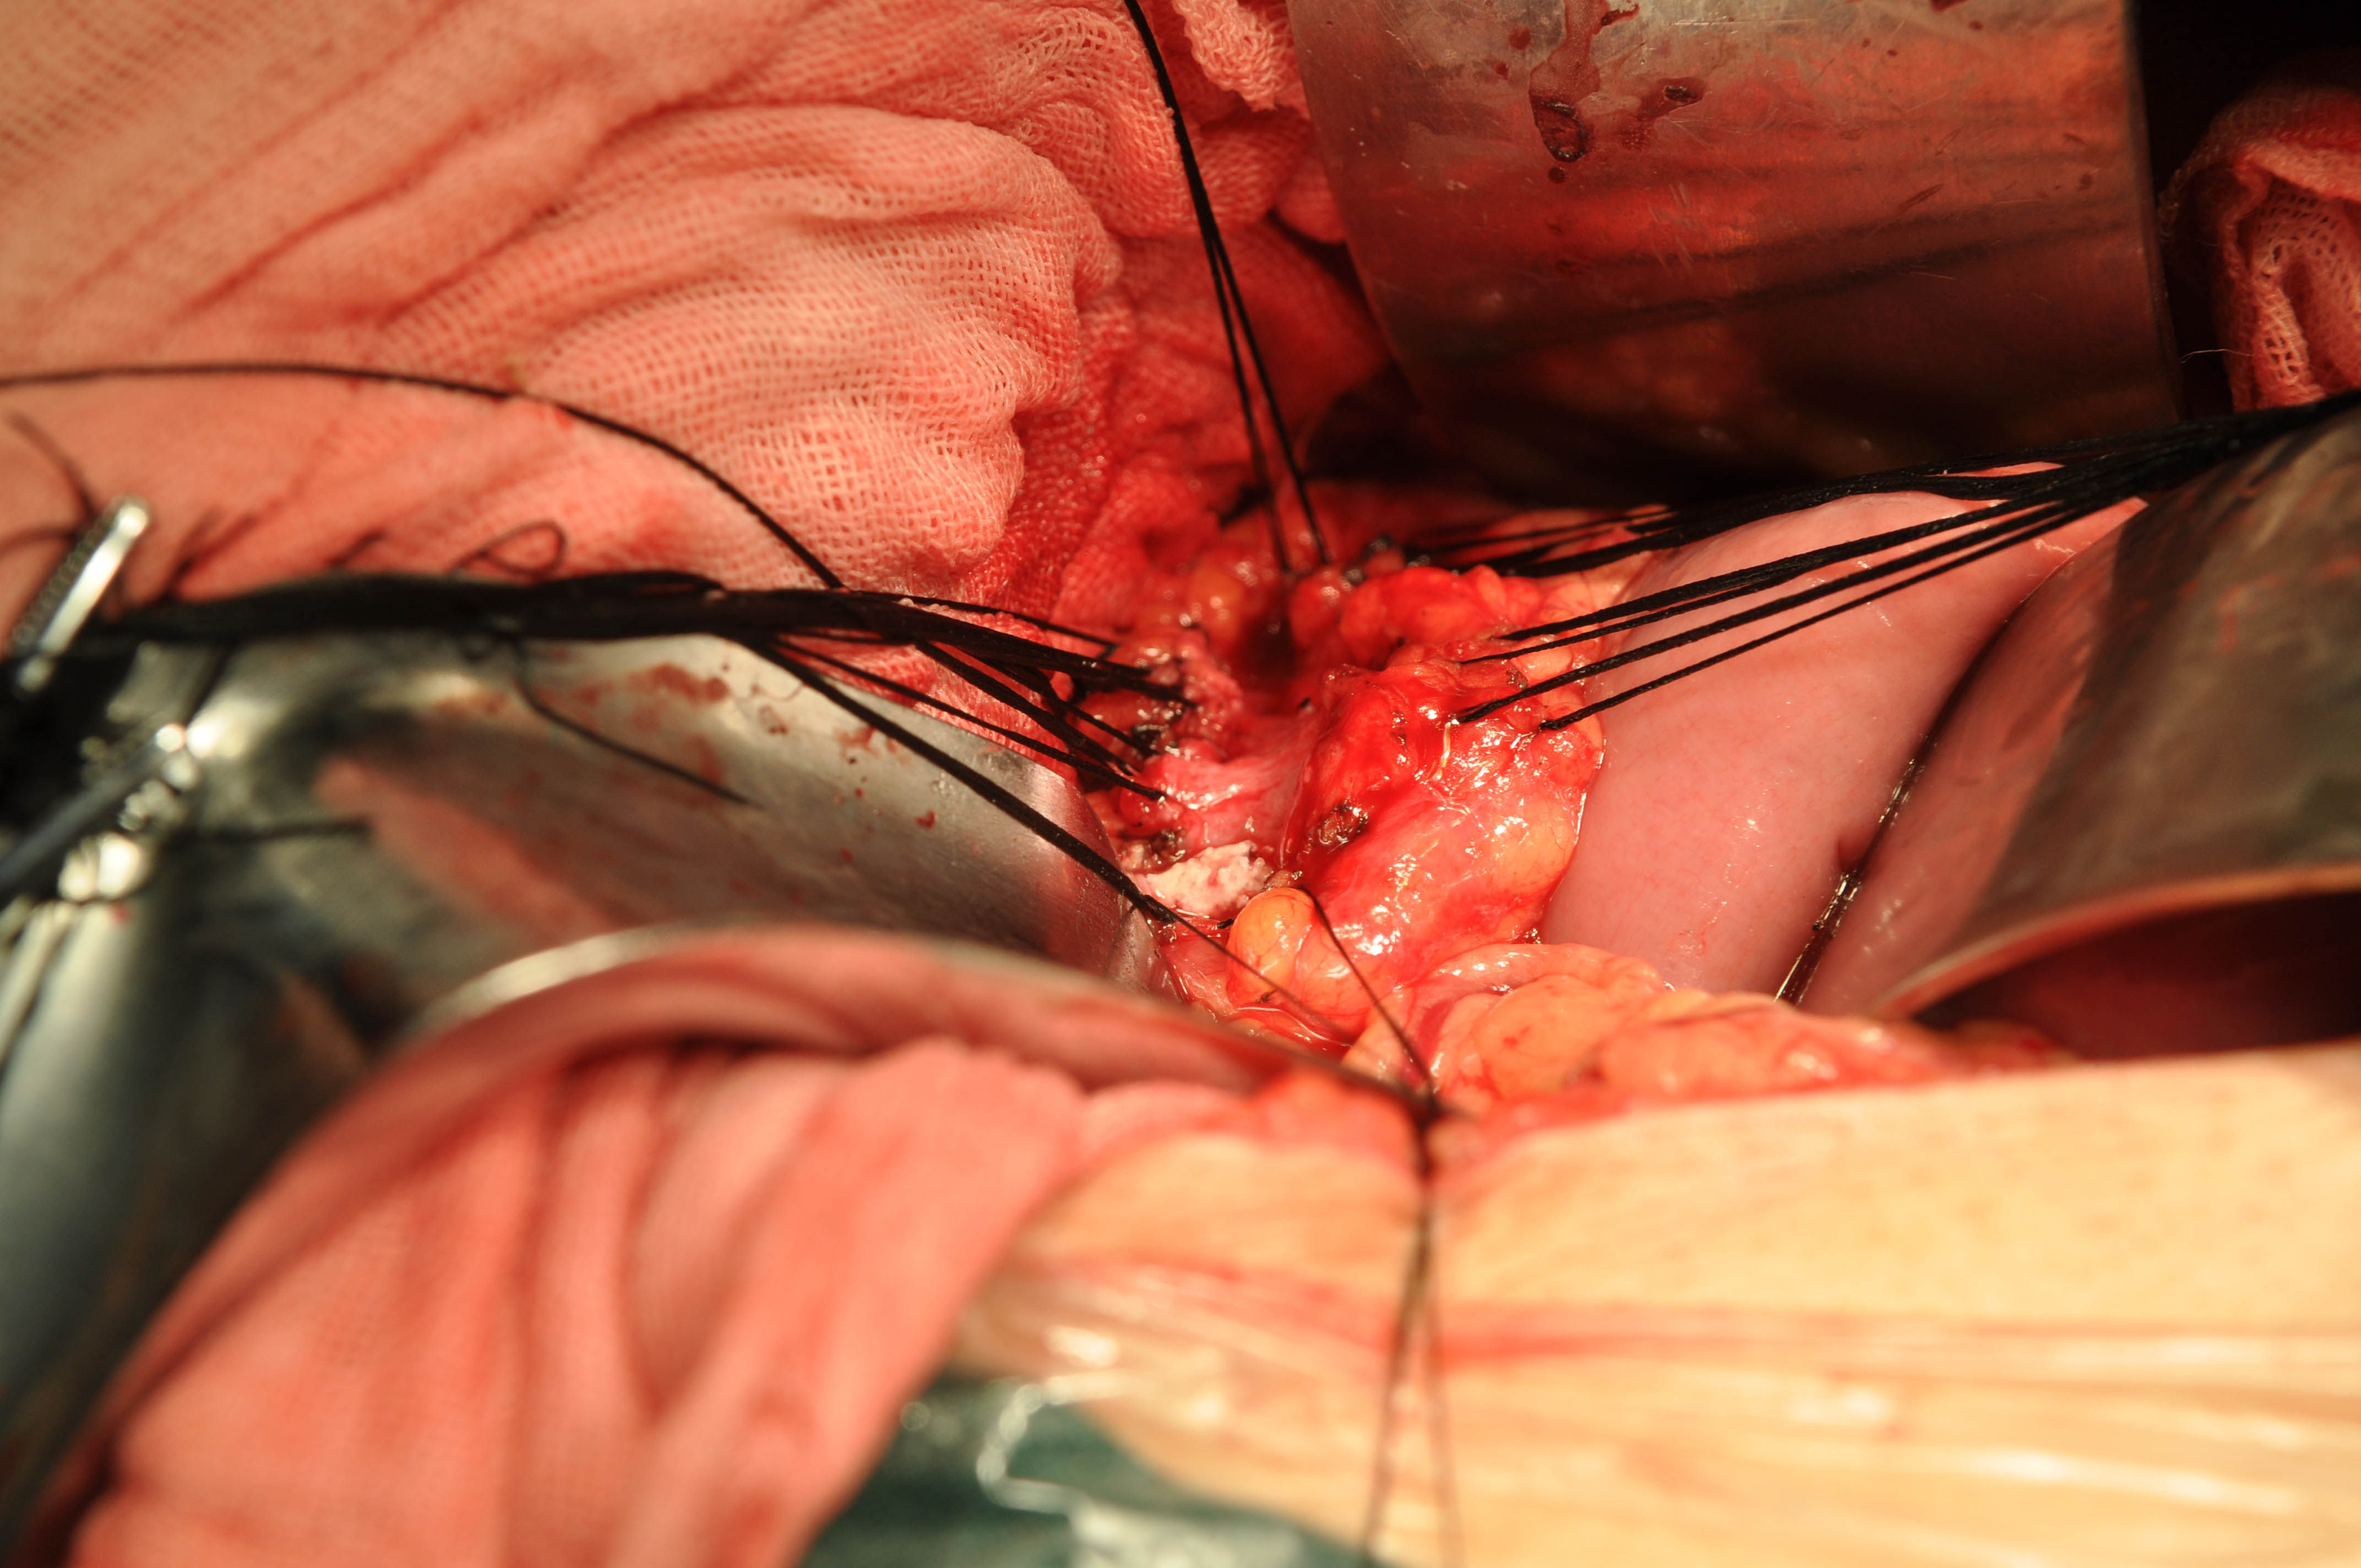

胰腺颈部离断后见胰管内还有结石

图片尺寸720x480